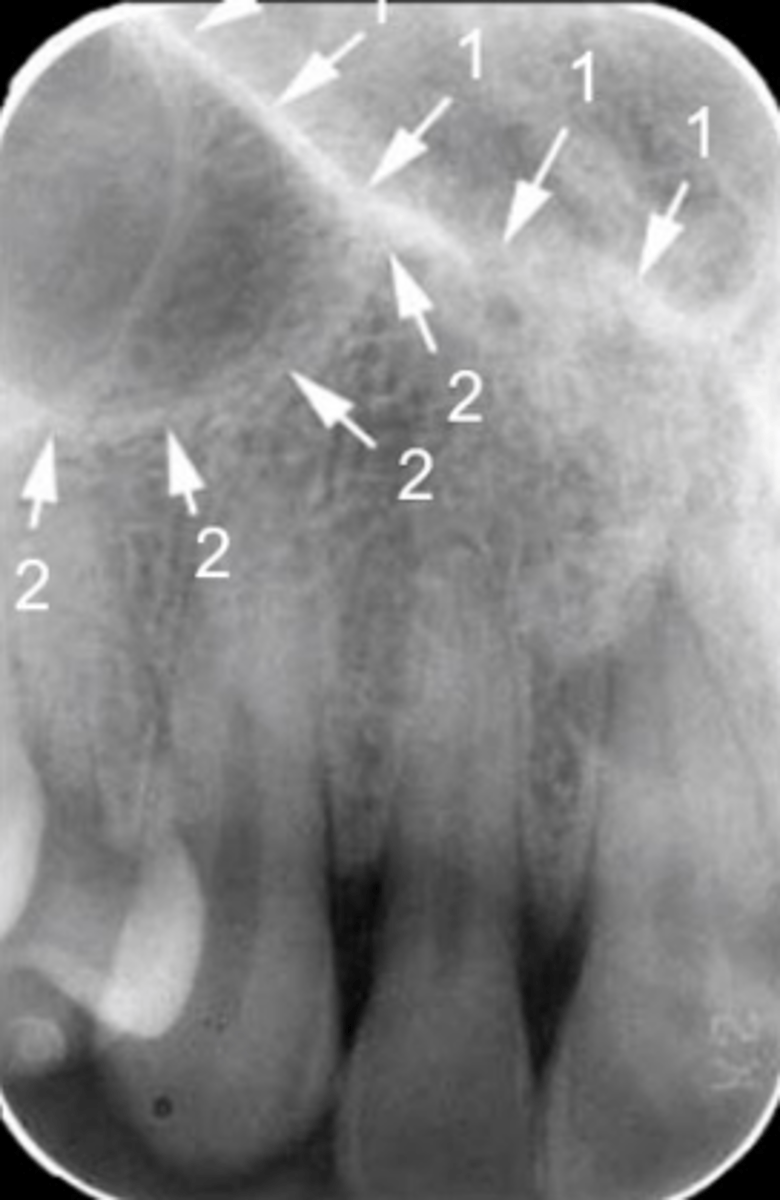

41

New cards

Floor of the maxillary sinus

Name the line indicated by arrows labeled #2.

<p>Name the line indicated by arrows labeled #2.</p>

65

Floor of the nasal cavity

Name the line indicated by arrows labeled #1.

<p>Name the line indicated by arrows labeled #1.</p>